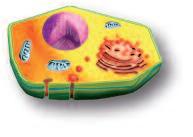

Normalmente, le cellule del nostro corpo sono inserite in una rete di collagene e di altre molecole del tessuto connettivo che le mantengono al loro posto. Affinché le cellule tumorali possano crescere, divenendo un tumore, e possano diffondersi in tutto il corpo, è necessario fendere questo isolamento del tessuto connettivo. A questo fine, ogni cellula del cancro produce ‘forbici biologiche’, ovvero degli enzimi proteolitici in grado di digerire il tessuto connettivo che circonda le cellule tumorali.

La pagina a fianco mostra l'immagine di una cellula tumorale reale, visualizzata al microscopio elettronico, che ingrandisce questa cellula 6500 volte rispetto alle sue normali dimensioni. Questo tipo di cellula prende il nome di carcinoma, cioè derivante da cellule epiteliali, il tipo di cellule che rivestono sia le superfici interne (polmoni, intestini) che esterne (pelle) del corpo.

Grazie a questo ingrandimento si possono identificare chiaramente alcune delle caratteristiche di tutte le cellule tumorali: a) l'enorme nucleo cellulare dalla forma insolita che spiega la loro grande capacità di riprodursi e b) la struttura non uniforme, complessa della superficie cellulare, che riflette una forte attività di secrezione di sostanze prodotte dalle cellule tumorali.

Una delle più importanti molecole secrete dalle cellule tumorali in grandi quantità sono gli enzimi a ‘forbice’ che digeriscono il collagene. Sono aggiunti graficamente a questa immagine, sotto forma di strutture simili ad un ‘pacman’ rosso.

“Forbici biologiche” – Enzimi

Naturalmente questi sfere, nella vita reale, sono molecole biologiche, proteine, che hanno la capacità di tagliare le fibre di collagene e di altre molecole del tessuto connettivo. L‘immagine sopra mostra che non c’è un solo tipo di 'pacman' ovvero di queste molecole, ma

Plasmin ogeni

Metal loproteinasi (MMP)

Digestione del tessut o connet tivo del tessuto connetti vo diversi tipi, quali il plasminogeno/plasmina e le metalloproteasi (strutture colorate tridimensionali). Queste molecole migliorano il loro effetto distruttivo attivandosi reciprocamente in forma di reazione a catena in cascata.